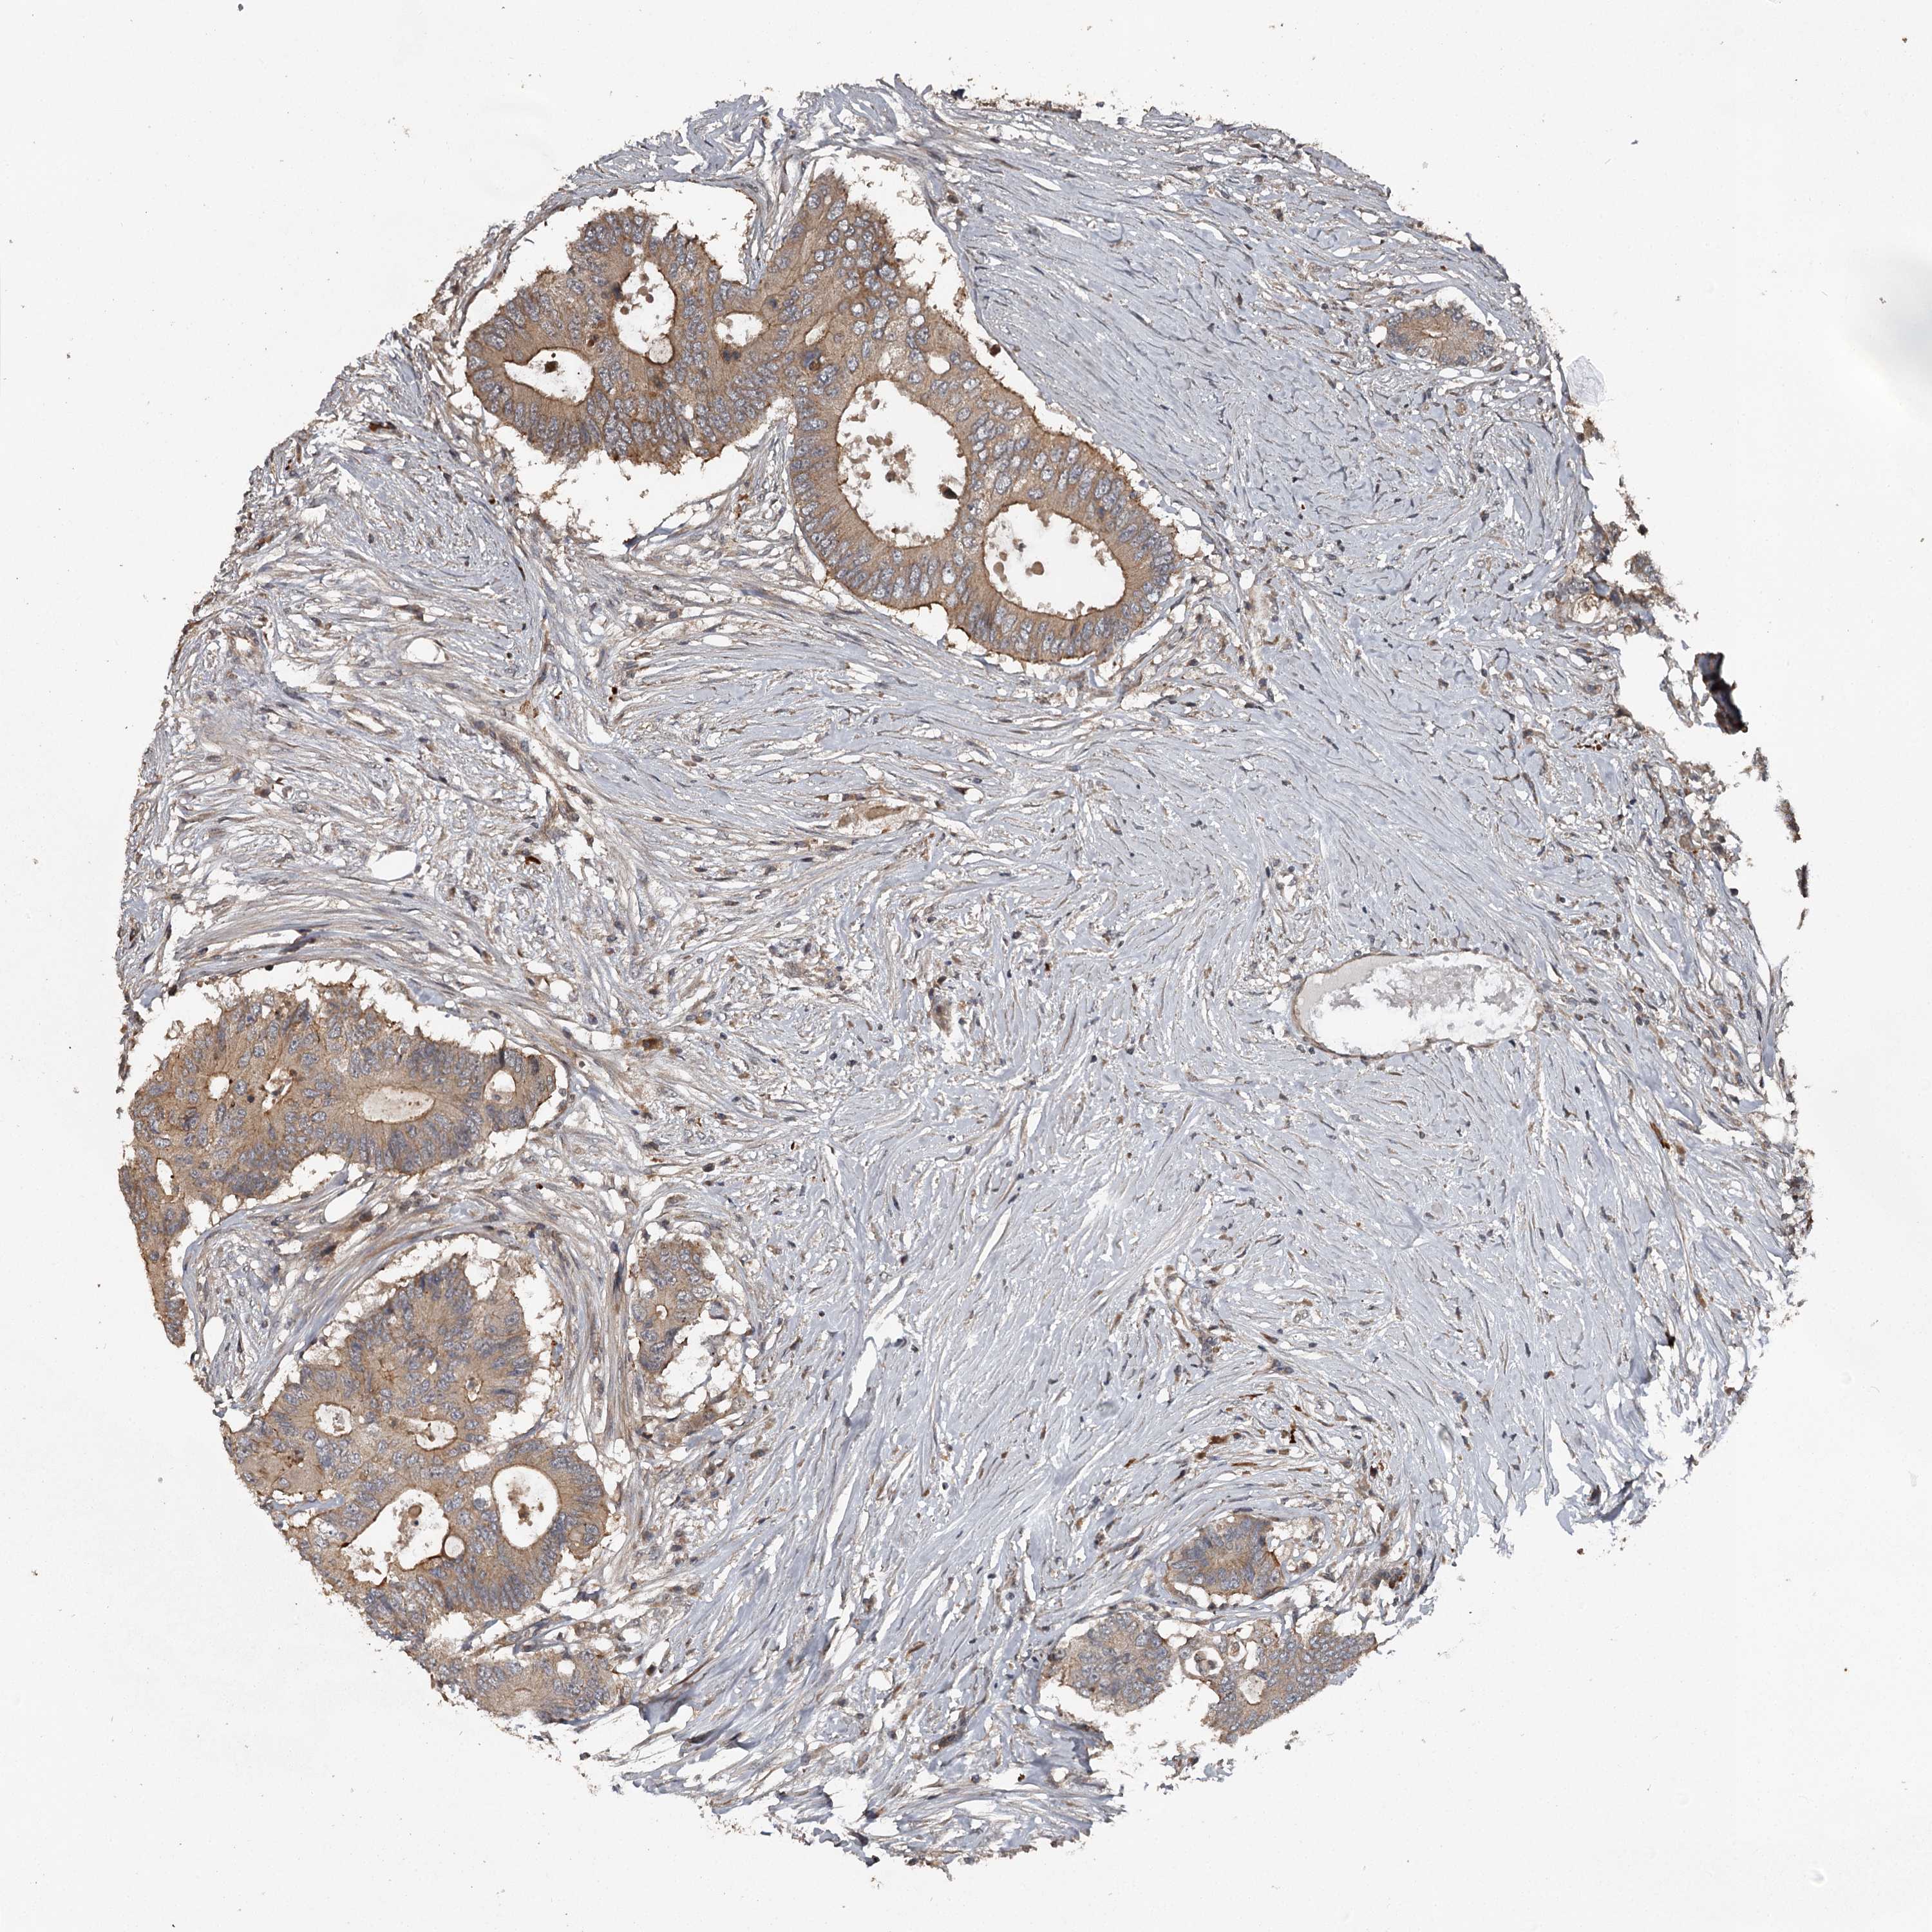

Colorectal cancer

Human cancer